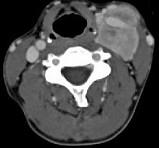

问题 女,39岁,左颈部可扪及一肿块,无发热,无疼痛,CT如图所示,最可能的诊断是()

选项 A.颈部神经鞘瘤 B.颈动脉体瘤 C.颈部神经纤维瘤 D.颈部海绵状血管瘤 E.颈动脉瘤

答案 B